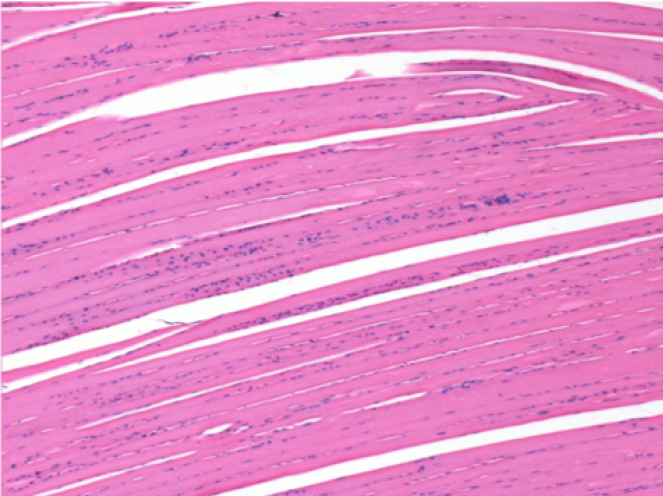

10 days after Endopeel Injection 0.1ml in the right pretibial muscle.

Here you may see the formation of the vacuoles which are surrounded by lymphocytes. Vacuoles are different from tissue necrosis . The presence of lymphocytes is related to the permeability of the cell membranes.